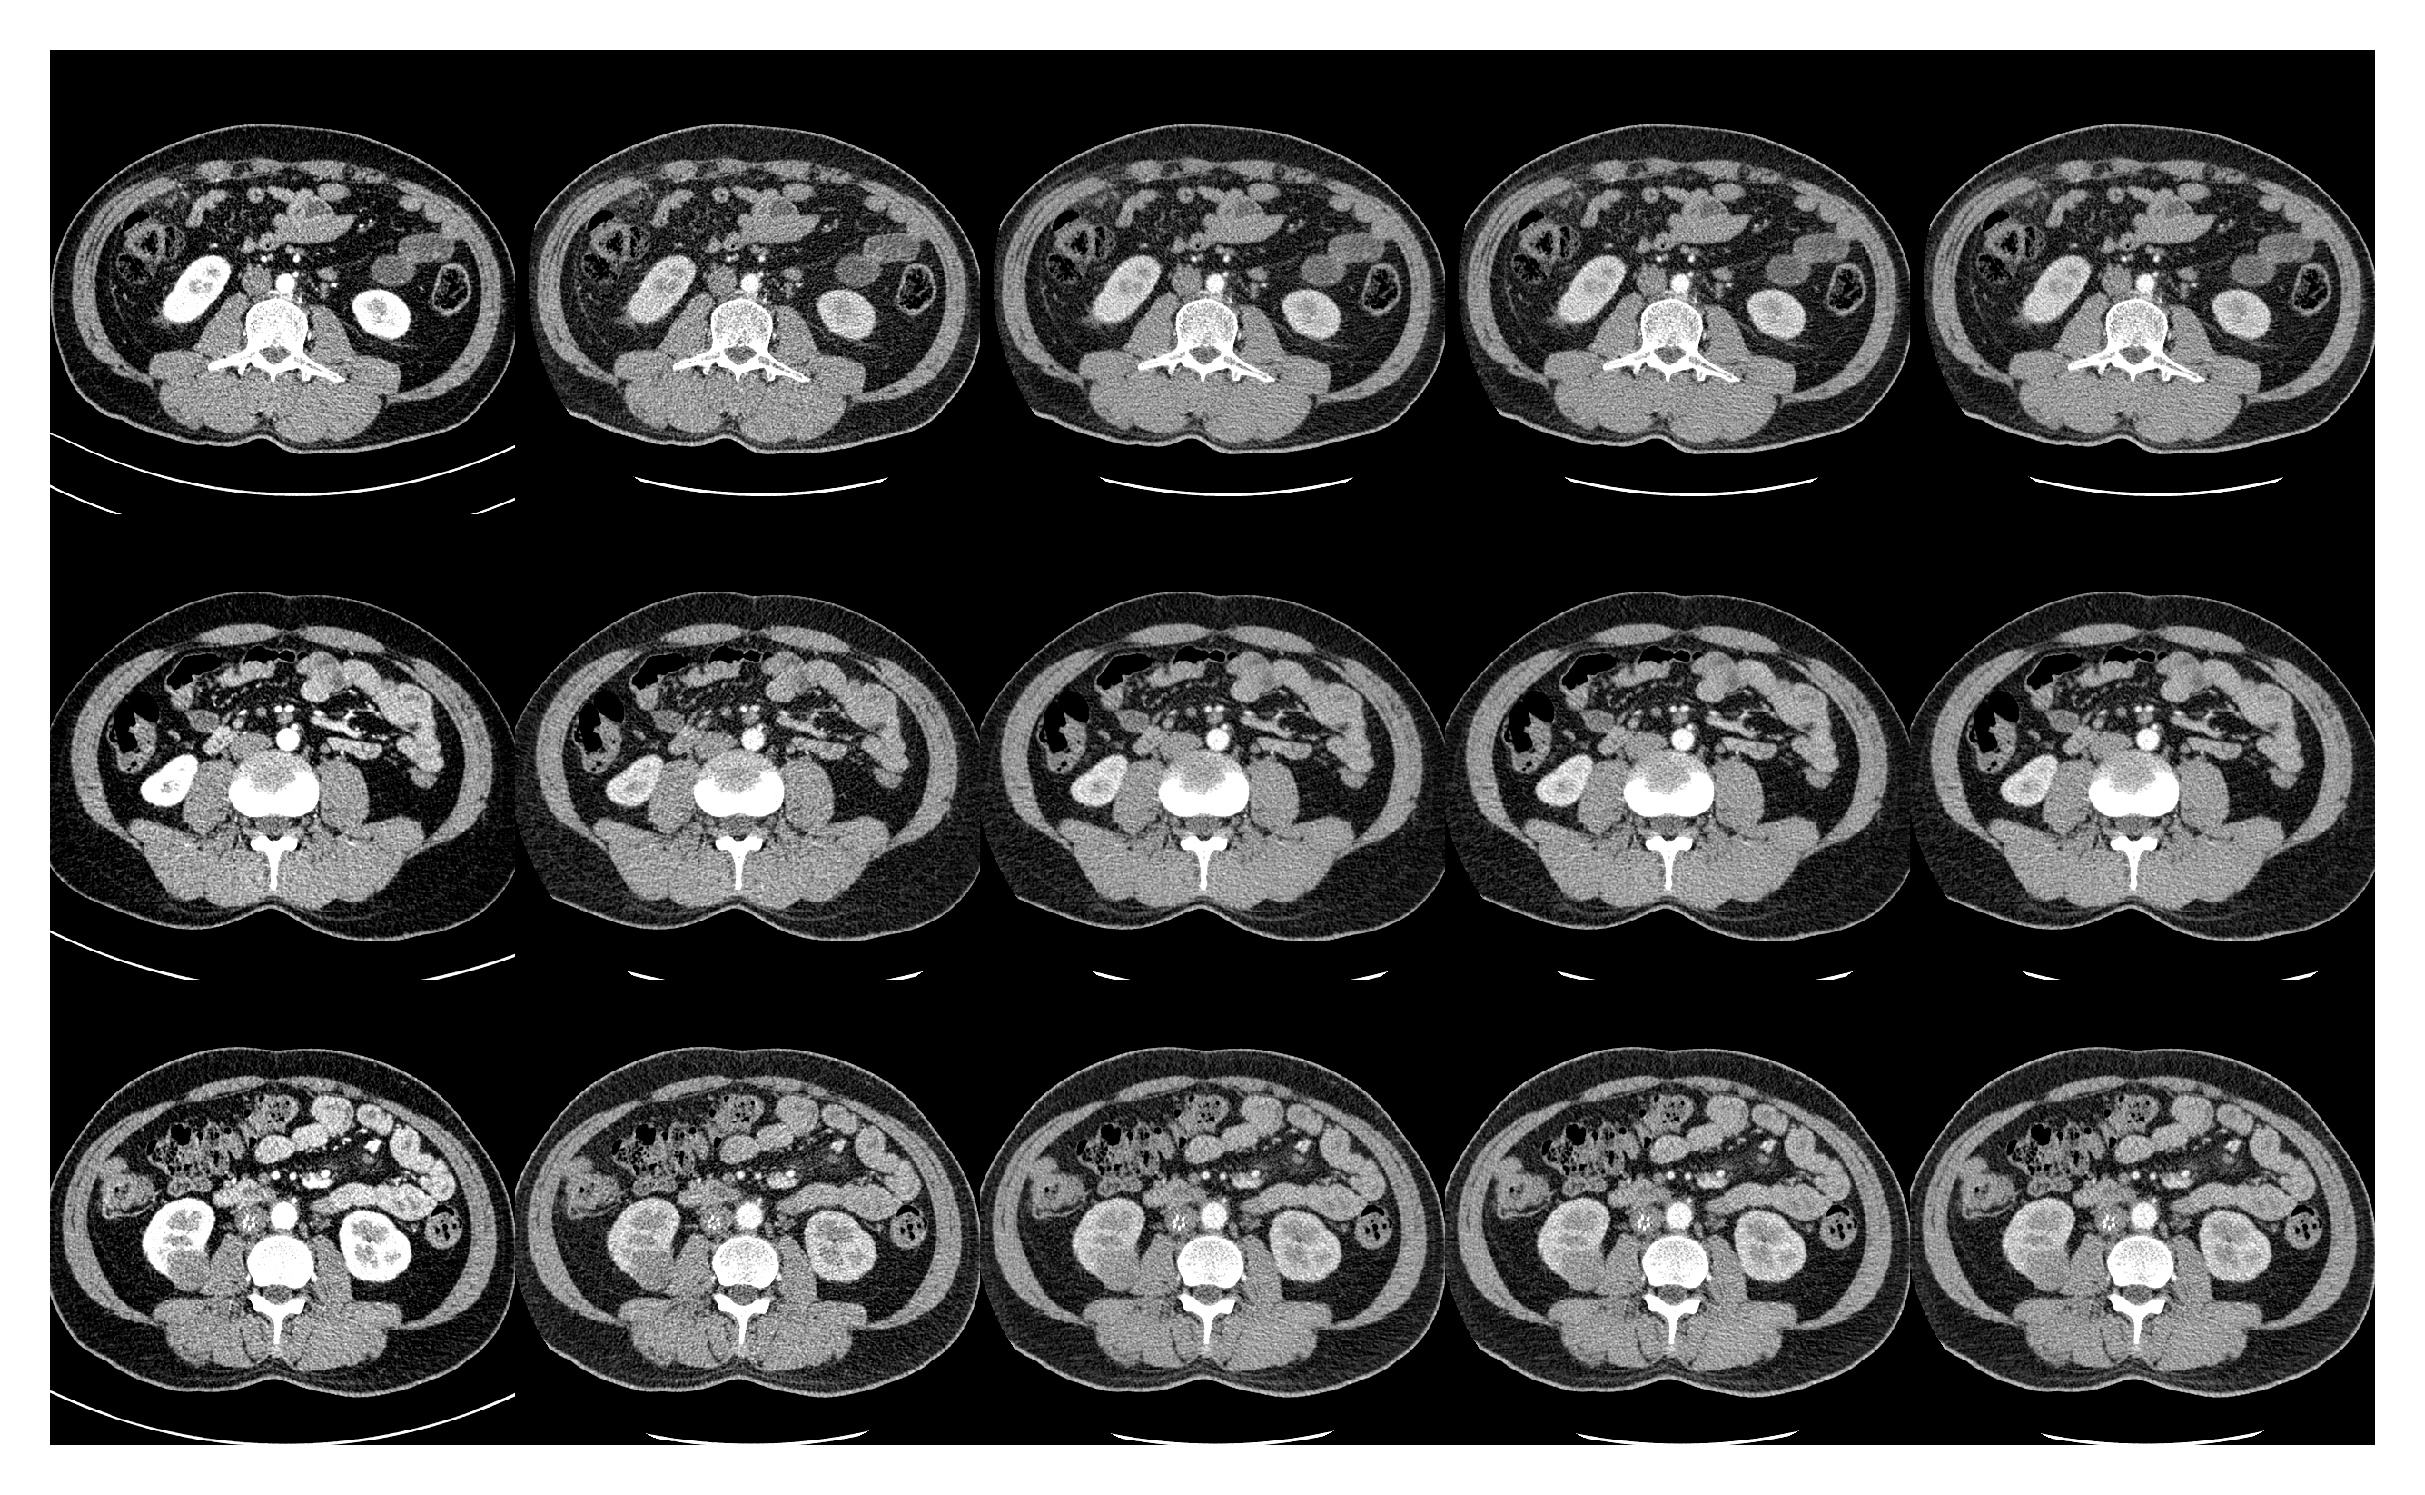

Refer to caption

Figure 9: Results on three testing slices for different geometry models. From left to right are original 100 kV images, original 140 kV images, parallel-beam results, equispacing fan-beam results and equiangular fan-beam results, respectively.

We tested the proposed method with several 2D CT geometries. Example results on a testing volume using different geometries are displayed in Fig. 9. All CT images are displayed with window width=300HU and center=50HU while difference images are displayed with window width=300HU and center=0HU. As can be seen, all models are able to provide competitive results which are highly consistent with the original high energy image. For better comparison, we also calculate quantitative metrics on those results (Table 4). The differences between the results obtained using the proposed method with different geometries are marginal and all of them are superior to our previous DL-DECT method which does not utilize the additional single-view projection. Overall, the proposed method reduces mean-squared error (averaged for all testing cases) from 1858.32 to 898.35 while increasing PSNR from 33.83 to 36.89 and SSIM from 0.8641 to 0.8744.